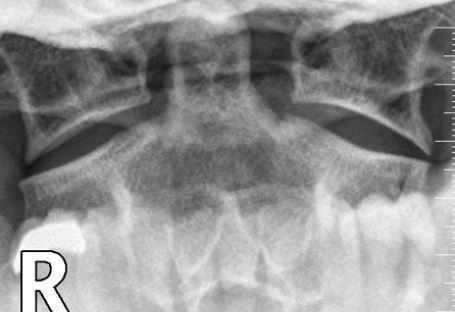

X-RAY QUIZ: Which finding is present on this image?

B: Sail sign

C: Meniscus sign